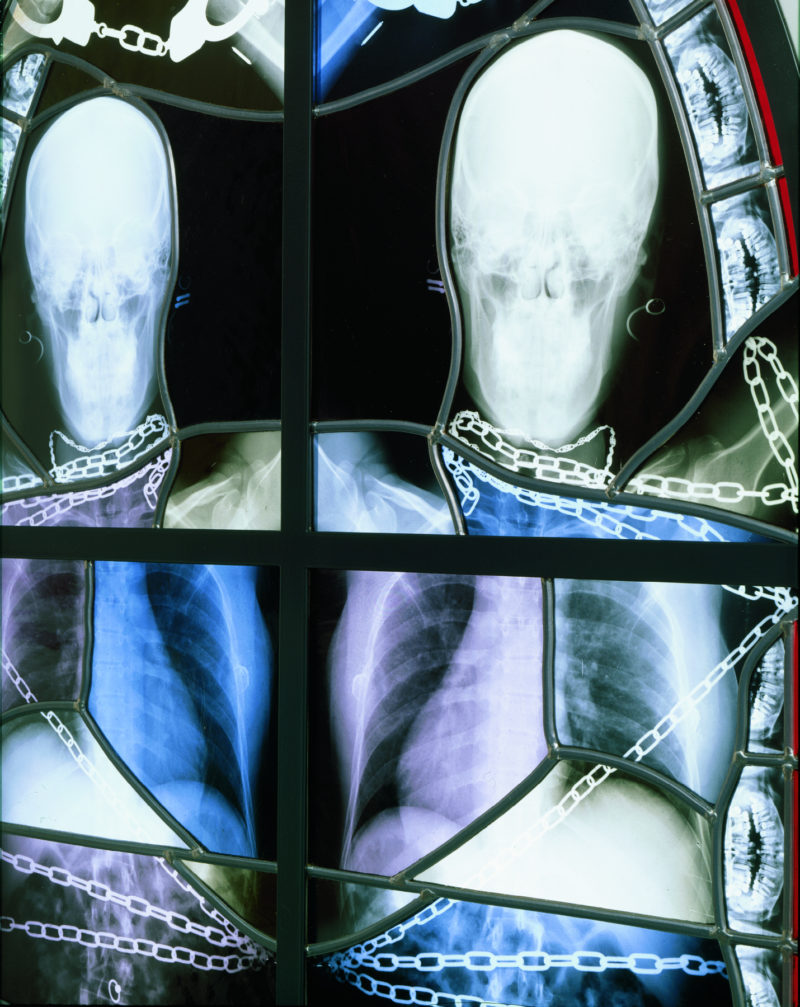

The windows themselves are constructed from authentic medical X‑ray images laminated between panels of glass and assembled within traditional Gothic lead frames. From afar they possess the luminous symmetry of medieval cathedral glass, but the figures revealed in the images are unmistakably skeletal: skulls, bones, and fragments of the human body (and sometimes those of animals) rendered with clinical precision. The sight is simultaneously beautiful and unsettling. These are stained glass windows that could plausibly belong in a church interior, yet their imagery evokes a cold anatomical reality rather than sacred narrative, and that was exactly the intent.

For the stained glass window works, Delvoye used X‑ray images taken during intimate encounters between two friends. The skeletal images produced by the radiographs were incorporated directly into stained-glass compositions and placed within Gothic-style window frames. From a distance the windows appear abstract, their luminous shapes resembling decorative patterns of light and color. Only when viewed closely do the anatomical elements emerge: skulls, teeth, spinal columns, and ribs forming intricate visual arrangements. In some panels the figures are clearly interacting, even kissing.

Rather than presenting his x‑ray images as one would if they were simple medical documents, Delvoye now incorporated them into elaborate stained-glass compositions modeled on the window structures of Gothic cathedrals. X‑ray films were mounted between panes of glass and framed with leaded tracery and laser-cut steel structures that echoed the intricate forms of seventeenth-century Flemish Baroque church windows. From a distance the panels resemble traditional ecclesiastical stained glass, glowing with the luminous qualities associated with historic cathedral interiors.

The imagery itself consists primarily of thousands of individual radiographic frames depicting skeletal structures, spinal columns, skulls, teeth, lungs, and various bodily gestures. In place of saints or biblical scenes, Delvoye created panels so that they would depict skeletal figures embracing, kissing, and interacting within the architectural frameworks of typical Gothic church windows. Yet the images reveal very little of the emotional dimension of human intimacy. Instead, the bodies appear as mechanical structures, bones and joints moving through space, suggesting that radiography reduces the human body to a kind of biological machine.

Delvoye also extended the project beyond human subjects. The series came to include X‑rays of animals such as pigs and snakes, along with scans of organic materials including intestines and sliced meats. Other panels move further toward abstraction, using swirling patterns of spinal columns or rows of teeth layered against backgrounds of deep red glass. The imagery oscillates between anatomical diagram and ornamental pattern, echoing the decorative rhythms of traditional stained-glass windows while simultaneously confronting viewers with the internal structures of the body.

The windows were organized into several thematic groups. Some panels represented classical muses, others referenced the months of the year, while a third group was designed specifically for architectural installations inside chapel-like structures fabricated from laser-cut steel. These chapels ranged from smaller architectural models to full-scale structures resembling miniature cathedrals.

When installed within chapel-like environments, constructed from his experience working with architectural iron forms, these figures function as anatomical ornaments, decorative elements replacing traditional sacred narratives. The visual language of religious architecture remains intact, but its iconography has been replaced by a meditation on bodily existence.

A key example of this approach appeared in the form of the work Chapelle from 2006. These installations were designed to be viewed inside of a fully realized architectural space, intensifying the spiritual dimension of the works. Visitors step into an enclosed space, built to resemble a chapel, containing the glowing radiographic panels, a viewing experience that mirrors the hidden, observational nature of medical imaging itself. By integrating colored glass with the radiographic material, Delvoye preserved the transparency of the X‑rays while recreating the atmospheric light effects associated with historical stained glass.

Inside the chapels the luminous panels produce a striking visual effect. Radiographic images of hips, skulls, ribs, and spines intertwine to form compositions that glow like traditional stained glass. Because X‑rays transmit light in much the same way as colored glass, the panels illuminate easily, producing a glittering yet macabre atmosphere. The resulting environment is both beautiful and unsettling.